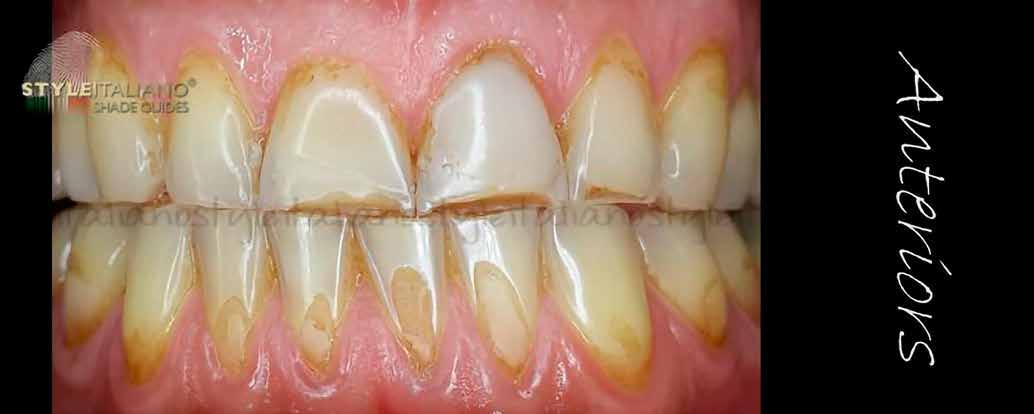

Egy 30 éves, negatív kórtörténettel rendelkező beteg azzal a kéréssel fordult hozzánk, hogy cseréljük ki az UR1 traumája után, 10 évvel korábban készült korábbi kompozit-helyreállítást.

A klinikai vizsgálat során az UR1 reagál a viabilitási tesztre, és az ugyanazon a napon készült röntgenfelvételen nem mutat periapikális elváltozásokat (1. ábra).

Az UR1 elszíneződött, és palatálisabb helyzetben van, mint az ellenoldali központi UL1 (2. ábra)

Az esztétikai elemzés a gingivális zenit aszimmetriáját mutatja az UR1 és az UL1 között. Parodontális szonda segítségével, plexusérzéstelenítés után, az IA

típusú funkcionális hám megváltozott passzív erupcióját igazoljuk Coslet és mtsai. osztályozása szerint (3. ábra)

A lehető legkonzervatívabb helyreállító kezelés elvégzése érdekében a páciensnél, figyelembe véve a megtartott fogelem korát és vitalitását, a tervezés és a diagnosztikai felviaszolás után a közvetlen kompozit-helyreállítás elvégzése mellett döntünk.